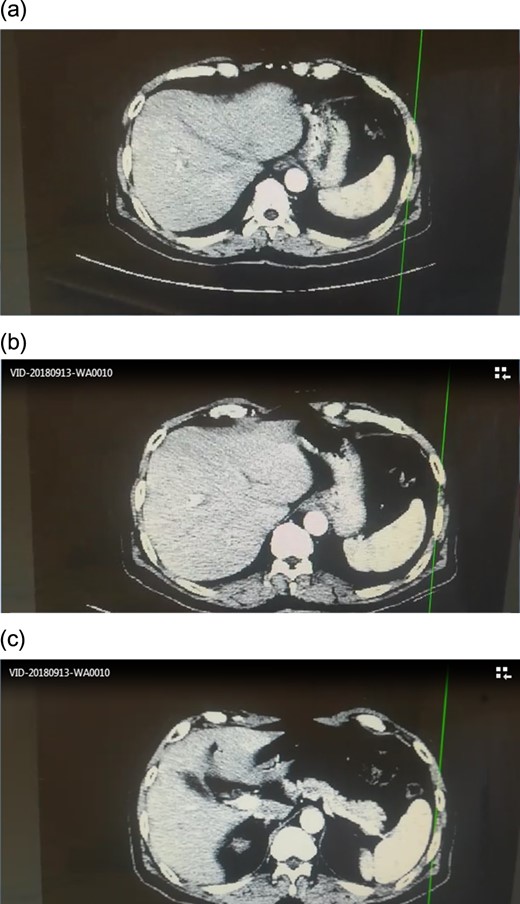

Angiographic CT after procedure confirmed the absence of celiac trunk, the absence of left gastric, the splenic artery arising from aorta directly and common hepatic artery arising from superior mesenteric artery.(Fig. 3)